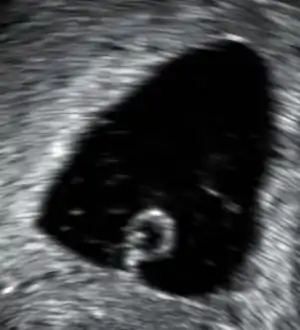

An ultrasound showing a gestational sac containing a yolk sac but no embryo.

An anembryonic pregnancy (also called an "empty sac" or "blighted ovum") is a condition where the gestational sac develops normally, while the embryonic part of the pregnancy is either absent or stops growing very early. This accounts for approximately half of miscarriages. All other miscarriages are classified as embryonic miscarriages, meaning that there is an embryo present in the gestational sac. Half of embryonic miscarriages have aneuploidy (an abnormal number of chromosomes).[47]